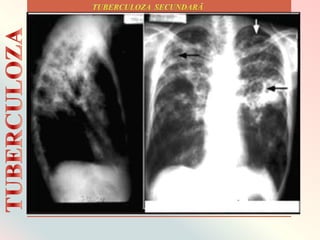

Săgețile albe indică infecția în

ambii plămâni. Săgețile negre arată

cavitatea care s-a format.